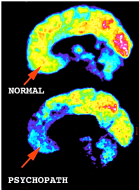

Become STRESSED from situations shown in the illustration.

Under stress they act first, figure things out later. They deal with problems & frustrations by going after more & more

external stimulation & adventure (similar to EnneaType 7s). When disappointed or restless, they think it’s time to re-create their (lagging or previous) successful public persona. They either find a new audience to charm, or resort to some grand gesture to reinforce their image & make them feel desirable/popular again (Ennea #3)

However, internally they suffer from a deep sense of emptiness, so intimacy becomes almost impossible, as they get increasingly detached from true emotional connections. As stress mounts, they get more agitated, chronically anxious, distracted & paranoid, but overactive, frivolous & too concerned with people’s opinions of them.